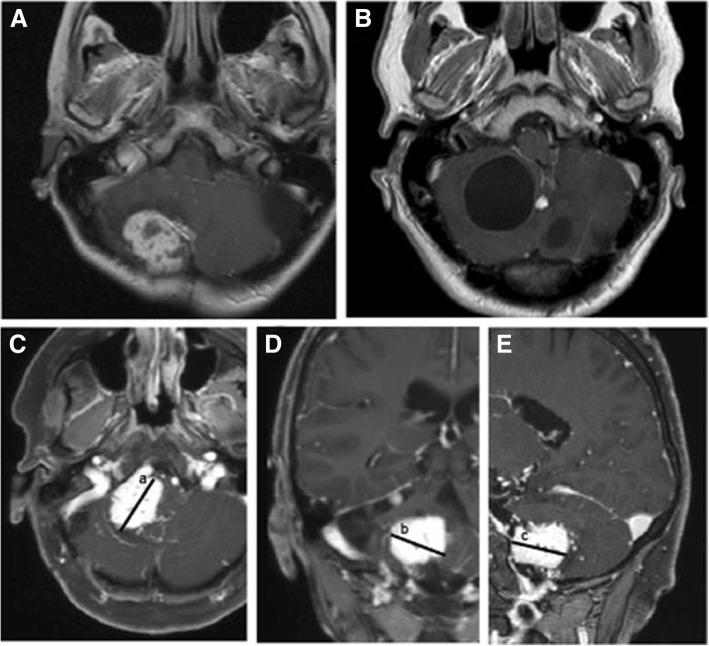

To elucidate the pathomechanism, we systematically investigated the relation between polyglobulia, serum EPO level, size of the solid tumor and associated cyst in hemangioblastomas. We prospectively evaluated hemoglobin and EPO levels in a series of 33 consecutive patients operated on hemangioblastomas in our center. We measured the size of the solid tumor and associated cyst in magnetic resonance imaging. Statistical evaluations were performed using the Fisher's exact test and student's t-test.

As a result five patients had elevated hemoglobin levels. Only one of these had an elevated serum EPO level. Of 26 patients with normal hemoglobin levels, 4 patients had elevated EPO levels.Patients with low or normal hemoglobin levels (84%) had an average tumor size of 0.8 cm, which differed significantly from patients with elevated hemoglobin levels (16%), who had an average solid tumor size of 8.0 cm ( < 0.05). We did not observe a significant correlation between EPO levels or polyglobulia and associated cysts.